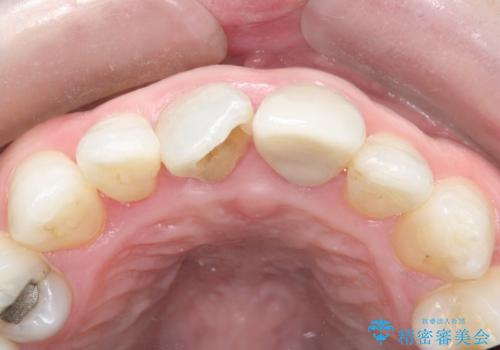

根管治療を行いセラミックを装着する計画としました。

ホワイトニングをセラミックを装着する前に行うことで、白くなった周りの歯に合わせたセラミッククラウンを装着することができました。